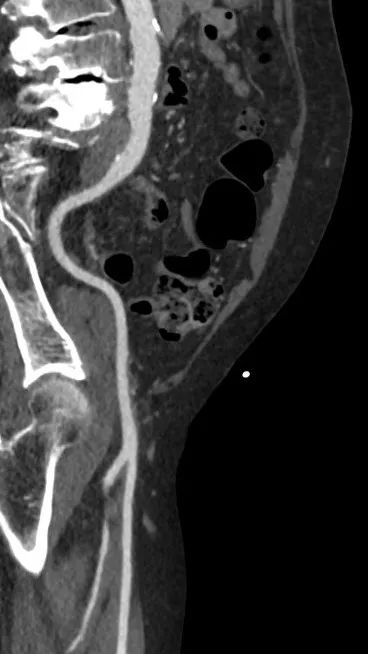

主动脉

右股

左股

升主动脉

长短径:39.7x37.6mm

(距瓣环40mm)